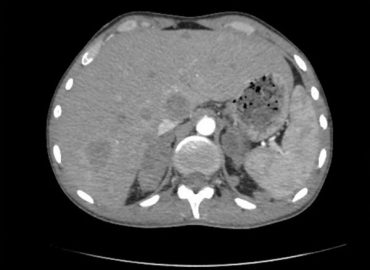

Mujer de 51 años. MC: anemia, náuseas, vómitos y diarrea.